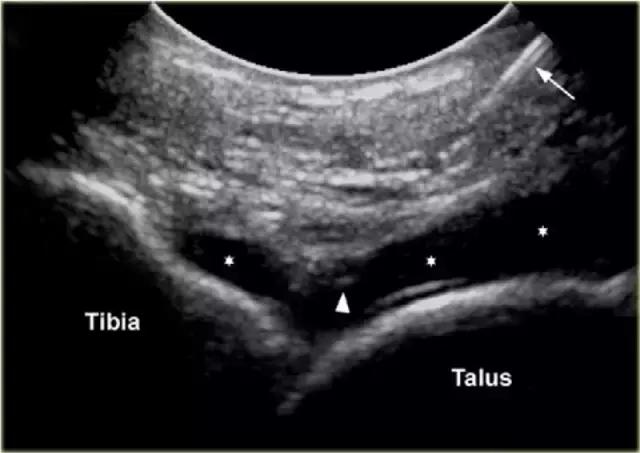

胫骨关节 CT或MR关节镜可用于查询韧带,骨软骨或软骨损伤,评价自由体或查询骨软骨病变的稳定性。针对踝关节(胫骨关节)的注射,患者仰卧,足部轻微的跖屈。用超声波检查胫骨关节的内侧,以确定合适的注射部位,同时检查任何过量的关节液。我们使用小型弯曲阵列8 MHz传感器,但如果优选,可以使用18-12 MHz线性阵列传感器。 探头的长轴保持在矢状面内。

通常为22号(长度:30mm)的针被引入与在前关节空间的内侧上的换能器的长成像轴线,内侧到前胫骨韧带,避免韧带和血管。应该确定距骨穹顶和悬垂的前胫骨唇。 针头在胫骨远端成角度地进入远侧胫骨的腹侧唇下的关节,瞄准远侧胫骨的关节表面。感觉到接触,并且再次确保针尖离开胫骨软骨并且斜面面向接头。

将8-10ml的对比剂注入胫骨关节,并且看到前囊与流体一起膨胀。

患者不应该有疼痛而抵抗。